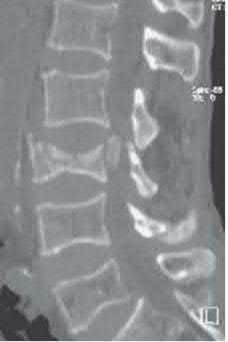

Question 5:

A 45-year-old male is involved in a high-speed motor vehicle collision and presents with the cervical spine radiograph findings typical of traumatic spondylolisthesis of the axis. Which of the following describes the primary mechanism of injury for this specific fracture pattern (Hangman's fracture)?

Correct Answer: Hyperextension and axial loading

Explanation:

A 'Hangman's fracture' is a traumatic spondylolisthesis of the axis (C2) involving fractures through the pars interarticularis. The classical mechanism of injury in modern trauma (e.g., unrestrained passenger hitting the windshield) is hyperextension and axial loading. Flexion-distraction typically causes Chance fractures, while flexion-compression typically causes anterior wedge or teardrop fractures.